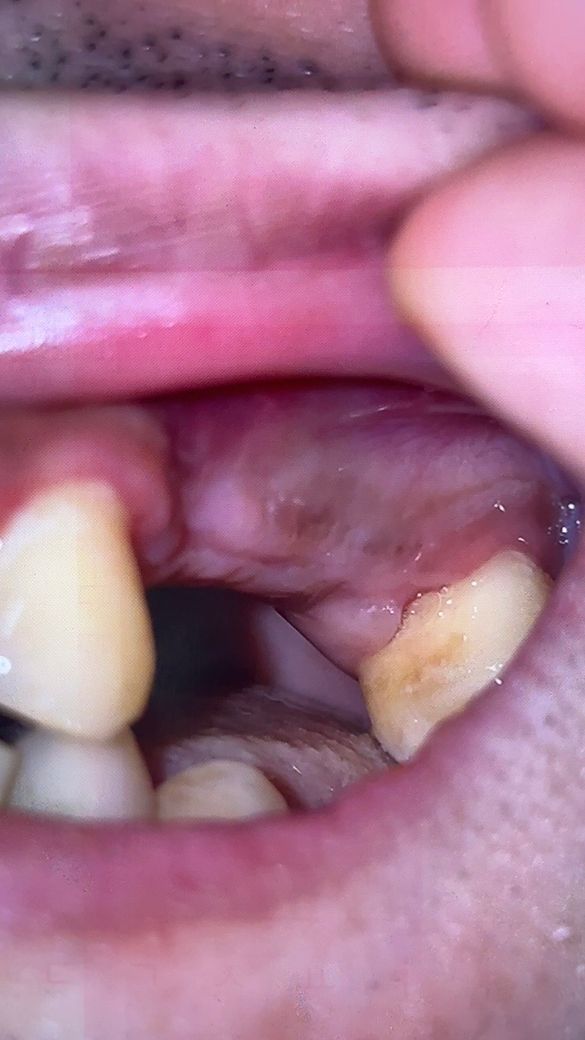

얼마전 프라그가 좀 끼인거같아 회사근처 치과로 내원 후 소독&제거를 받았는데 보시다시피 보철물사이에 검은공간이 보여서 혹시 주위염이 발생한건지 고견을 듣고싶습니다(구멍이 크진 않으나 저런 검은 공간이나 경계면?이라고 해야할지 잇몸과 보철물 사이의 검은부분도 신경이 쓰이네요..)

12/24일에 파노라마 찍은것과 보철물 식립전의 잇몸사진도 첨부하겠습니다

• 2번 째 사진

사진에 보이는는 정도는 괜찮습니다. 잇몸부위에 맞춰서 제작을 하지만 잇몸이 조금씩 내려가면서 약간 틈이 생긴거 같습니다.